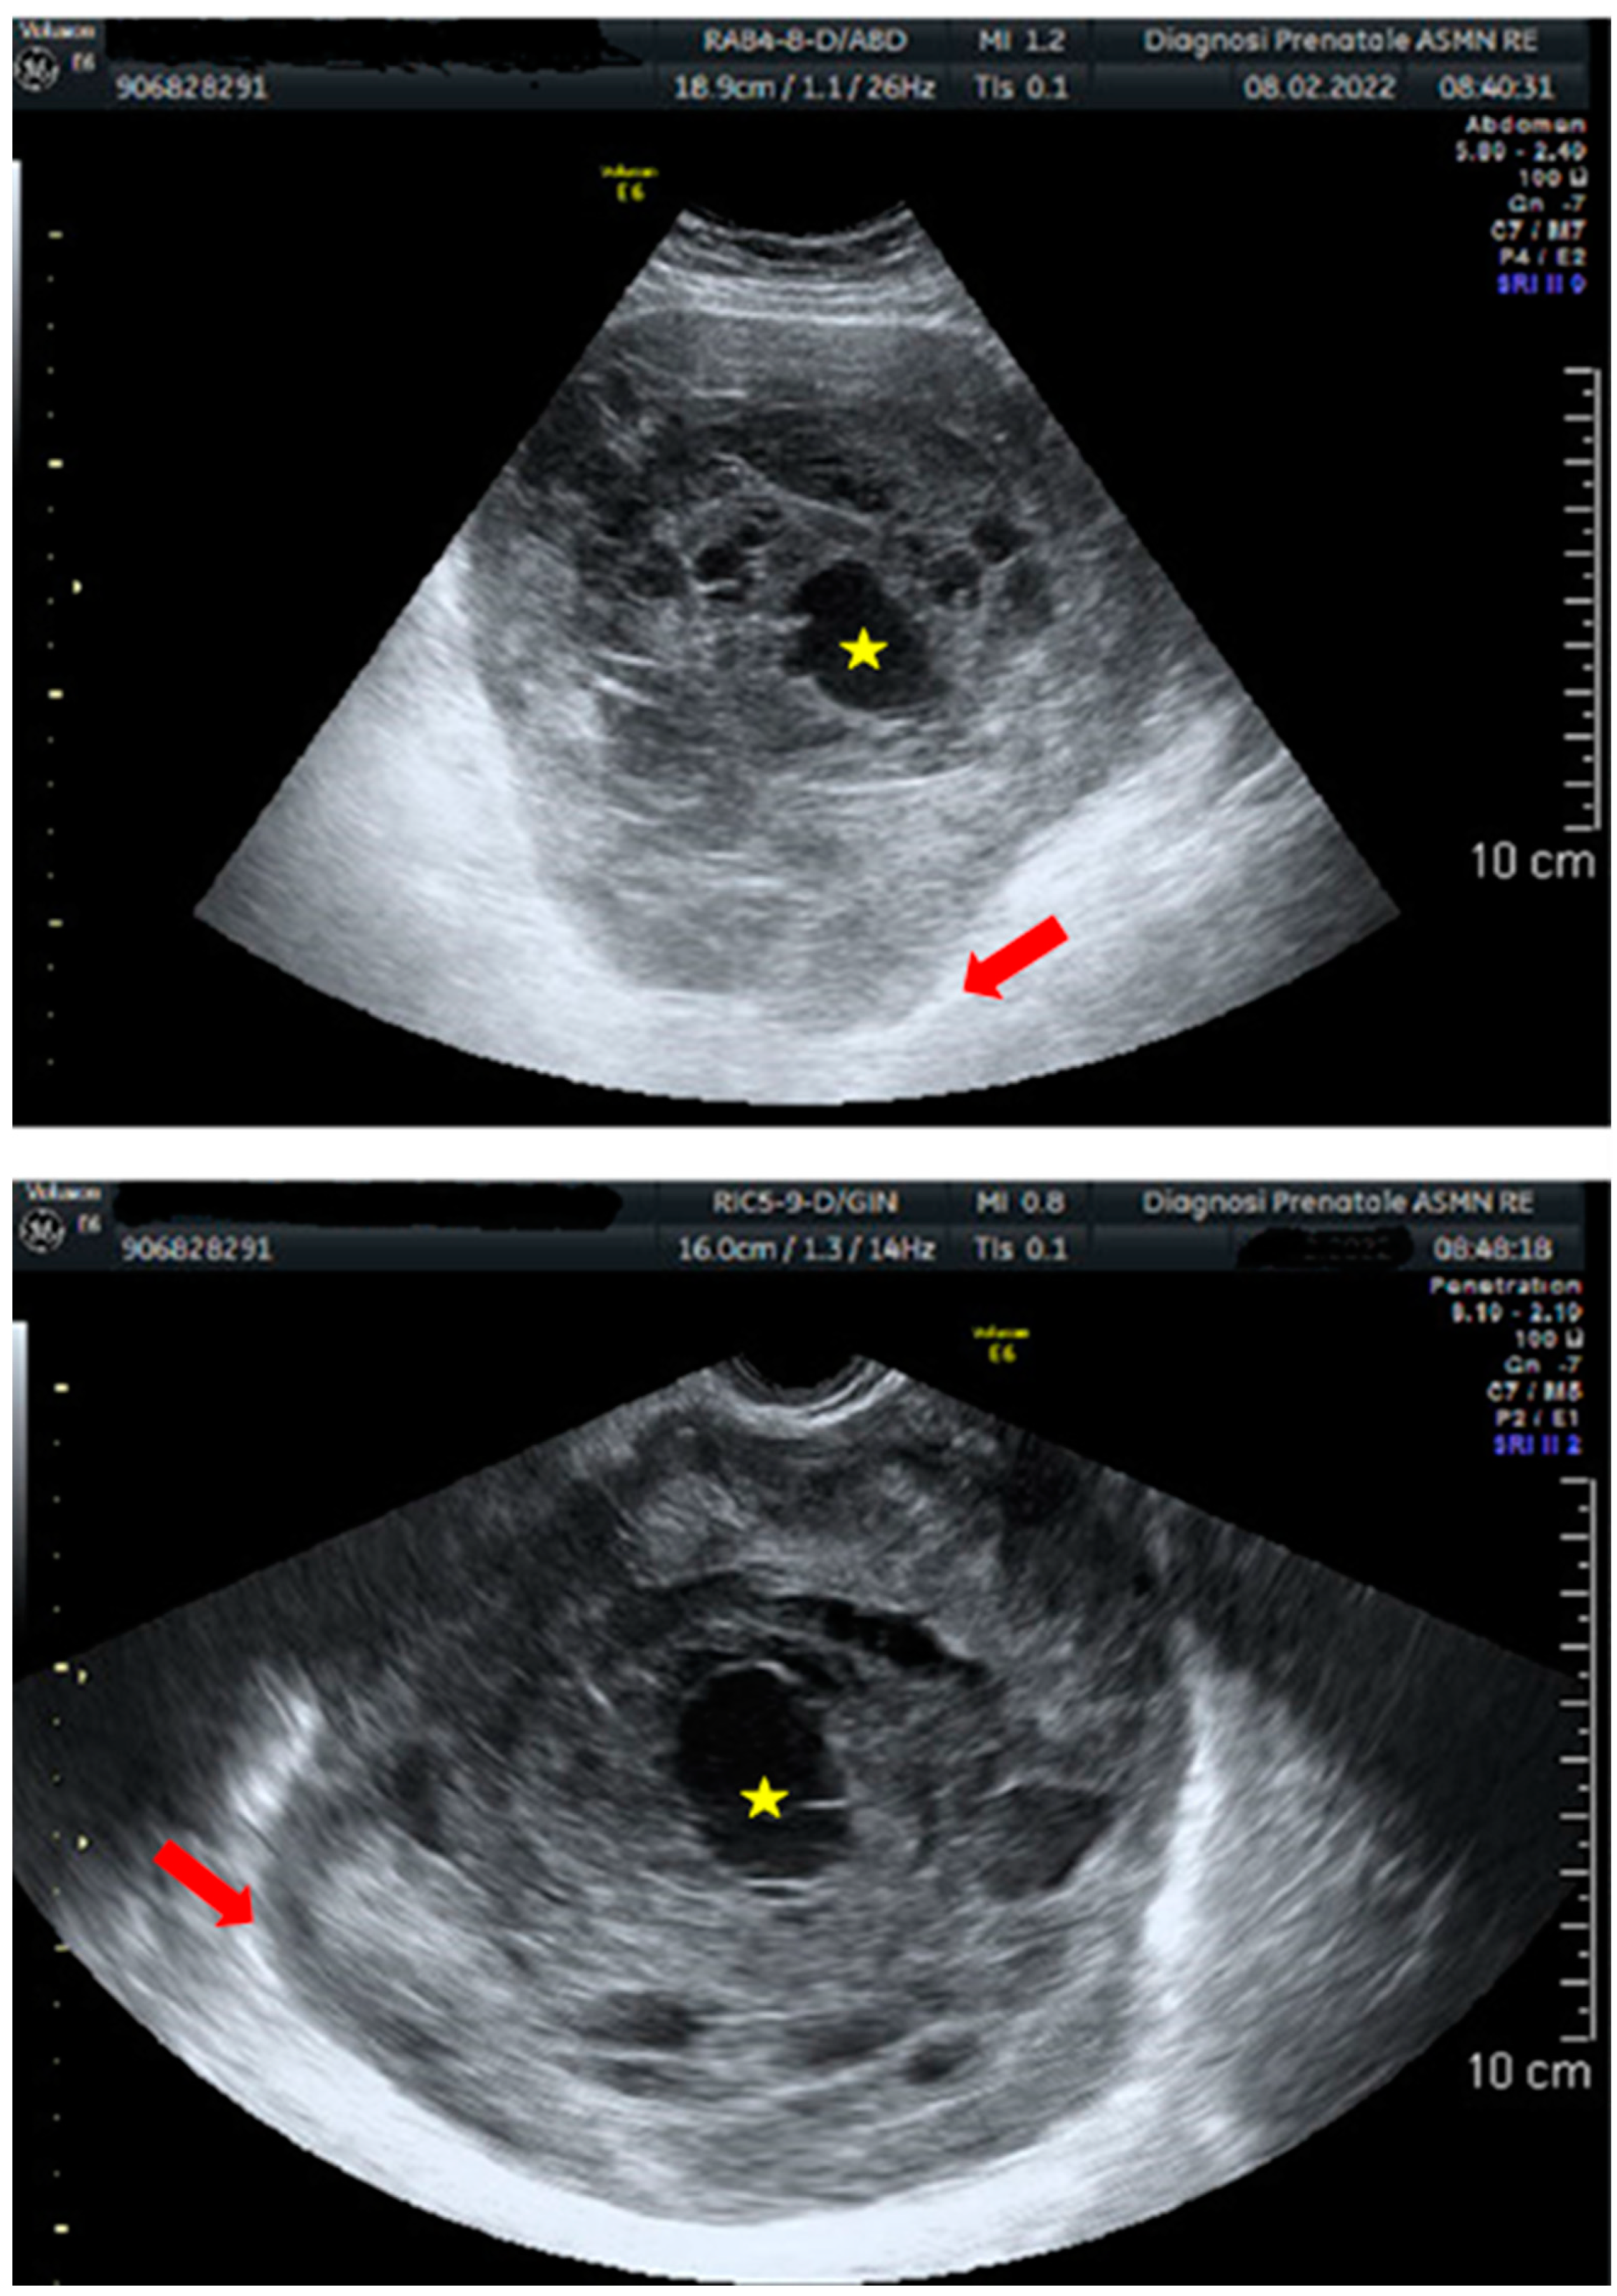

- Fischetti, A.; Rutigliani, M.; Romano, N.; Marinaro, E.L.; Puppo, C.; Gorlero, F.; Melani, E.F.; Rollandi, G.A. Imaging findings of ovarian leiomyosarcoma with histopathologic correlations. Eur. J. Obstet. Gynecol. Reprod. Biol. 2019, 236, 261–262. [Google Scholar] [CrossRef]